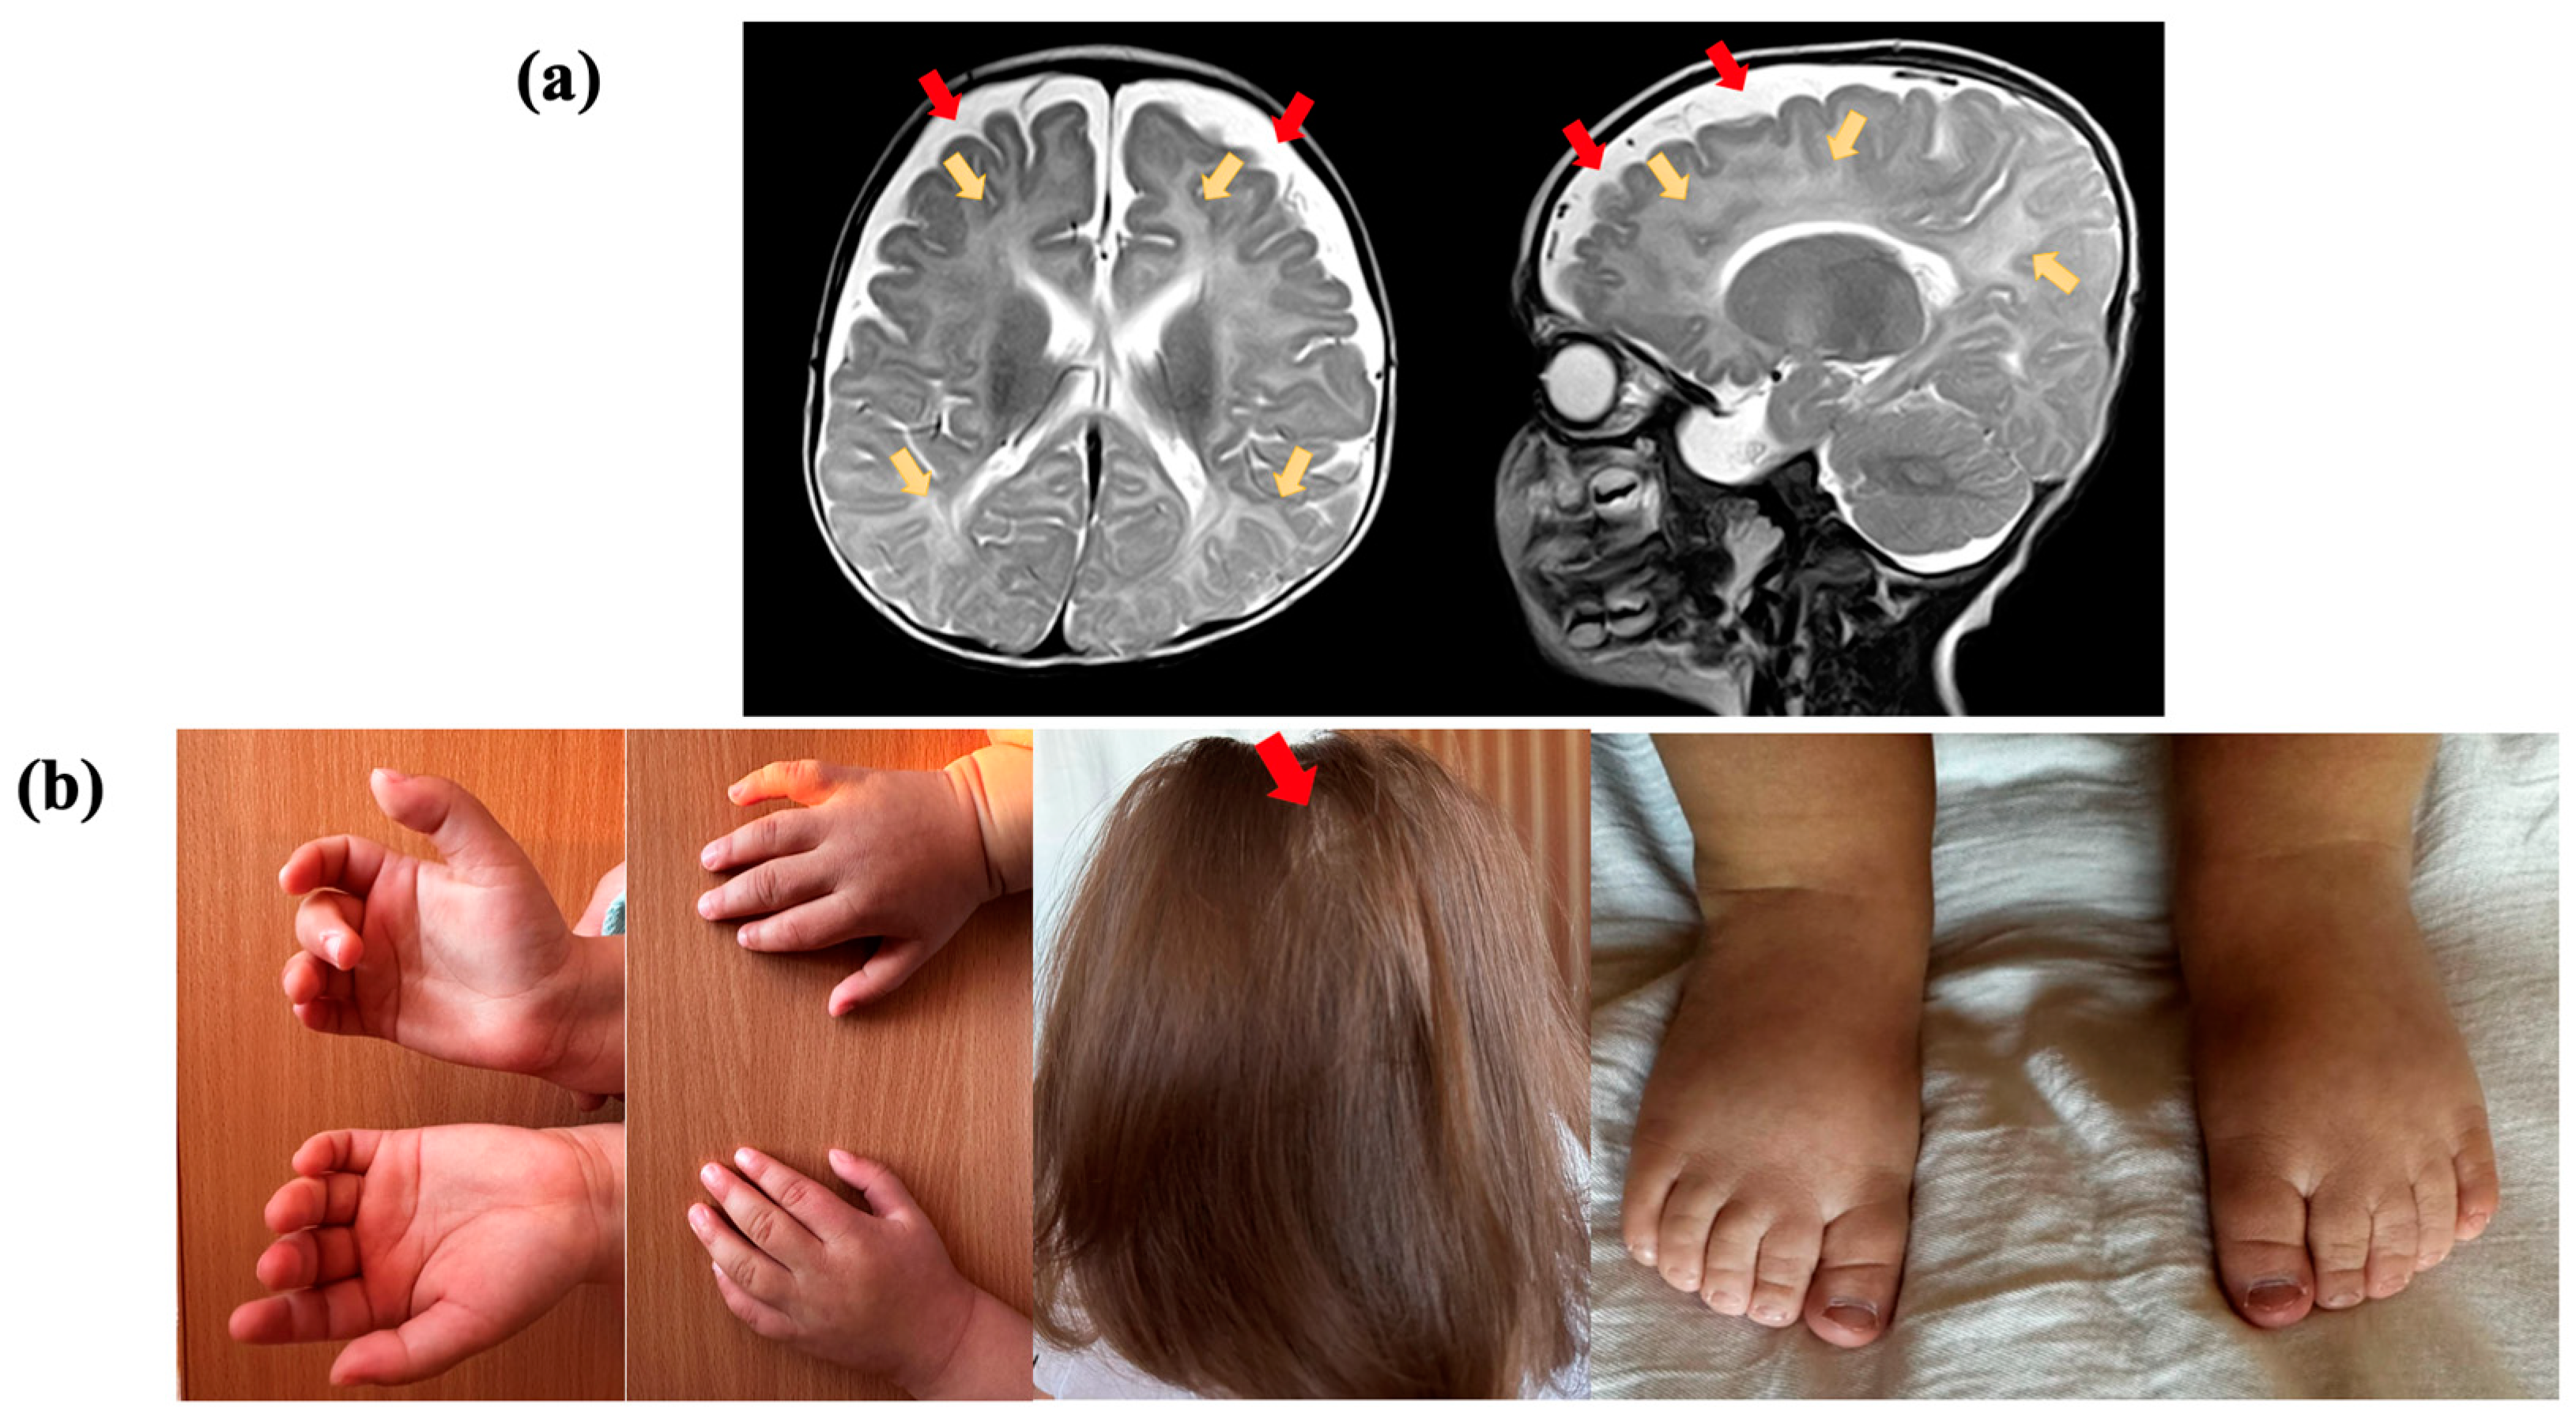

2.1. Clinical Evaluation